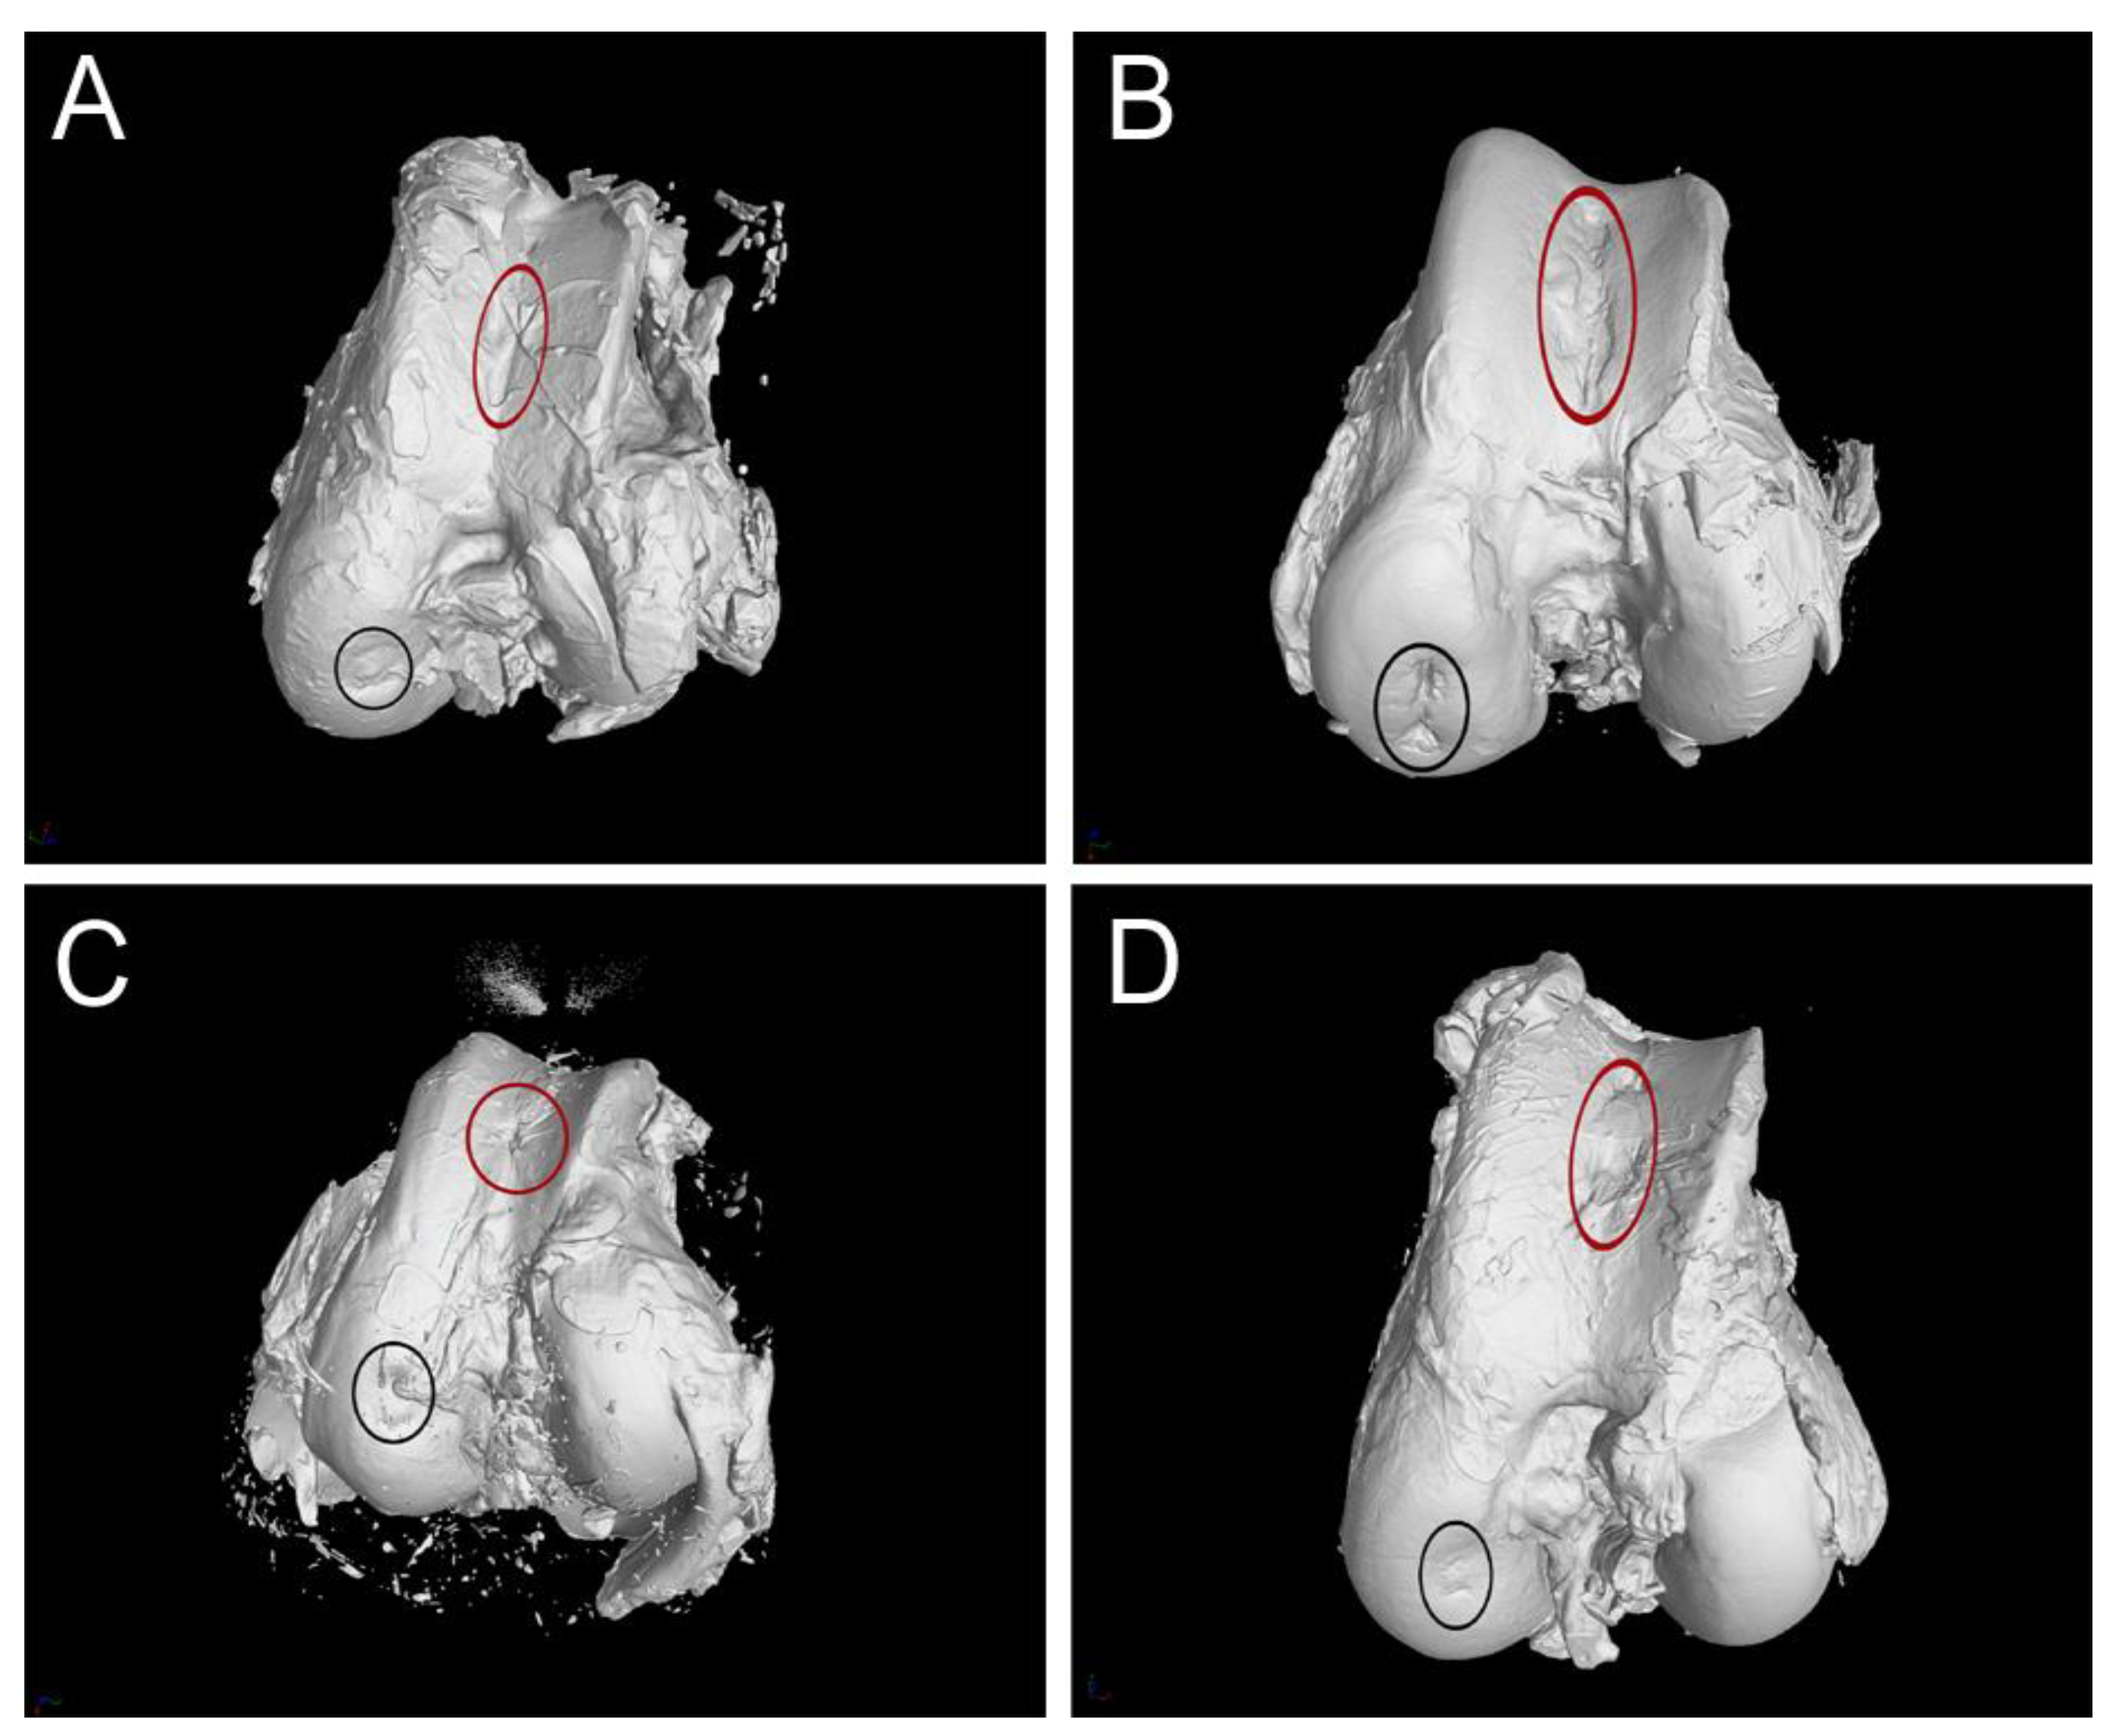

3.3. CT Evaluation

3.4. MRI Evaluation